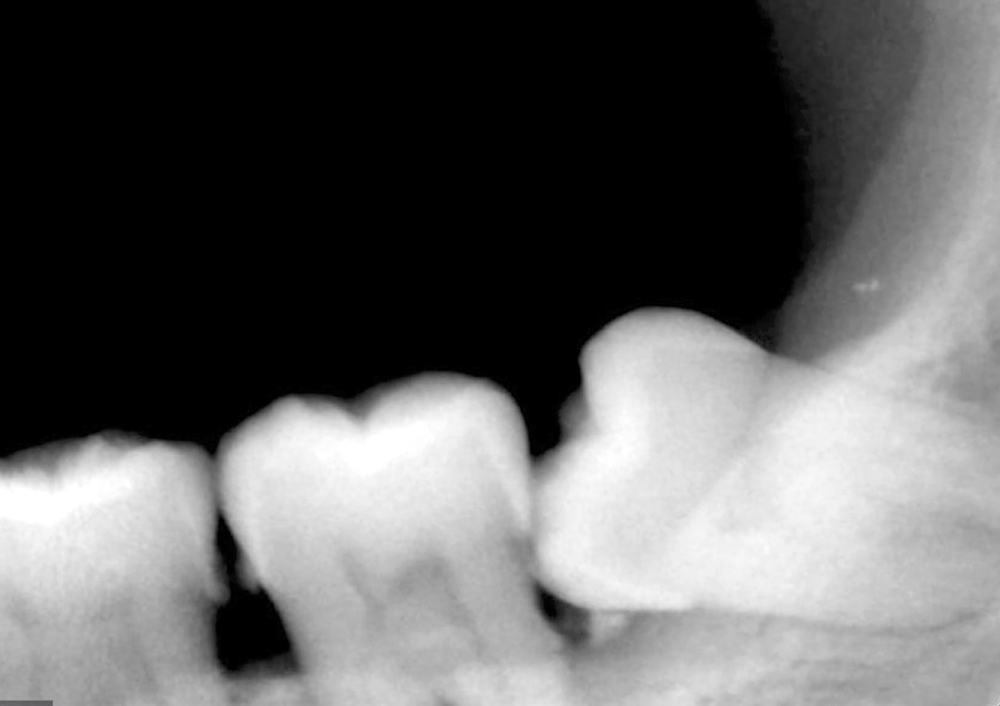

03. 수면 사랑니 발치 진행

실시간으로 환자의 맥박, 혈압,

산소포화도 등을 실시간으로

모니터링하면서 사랑니발치 진행